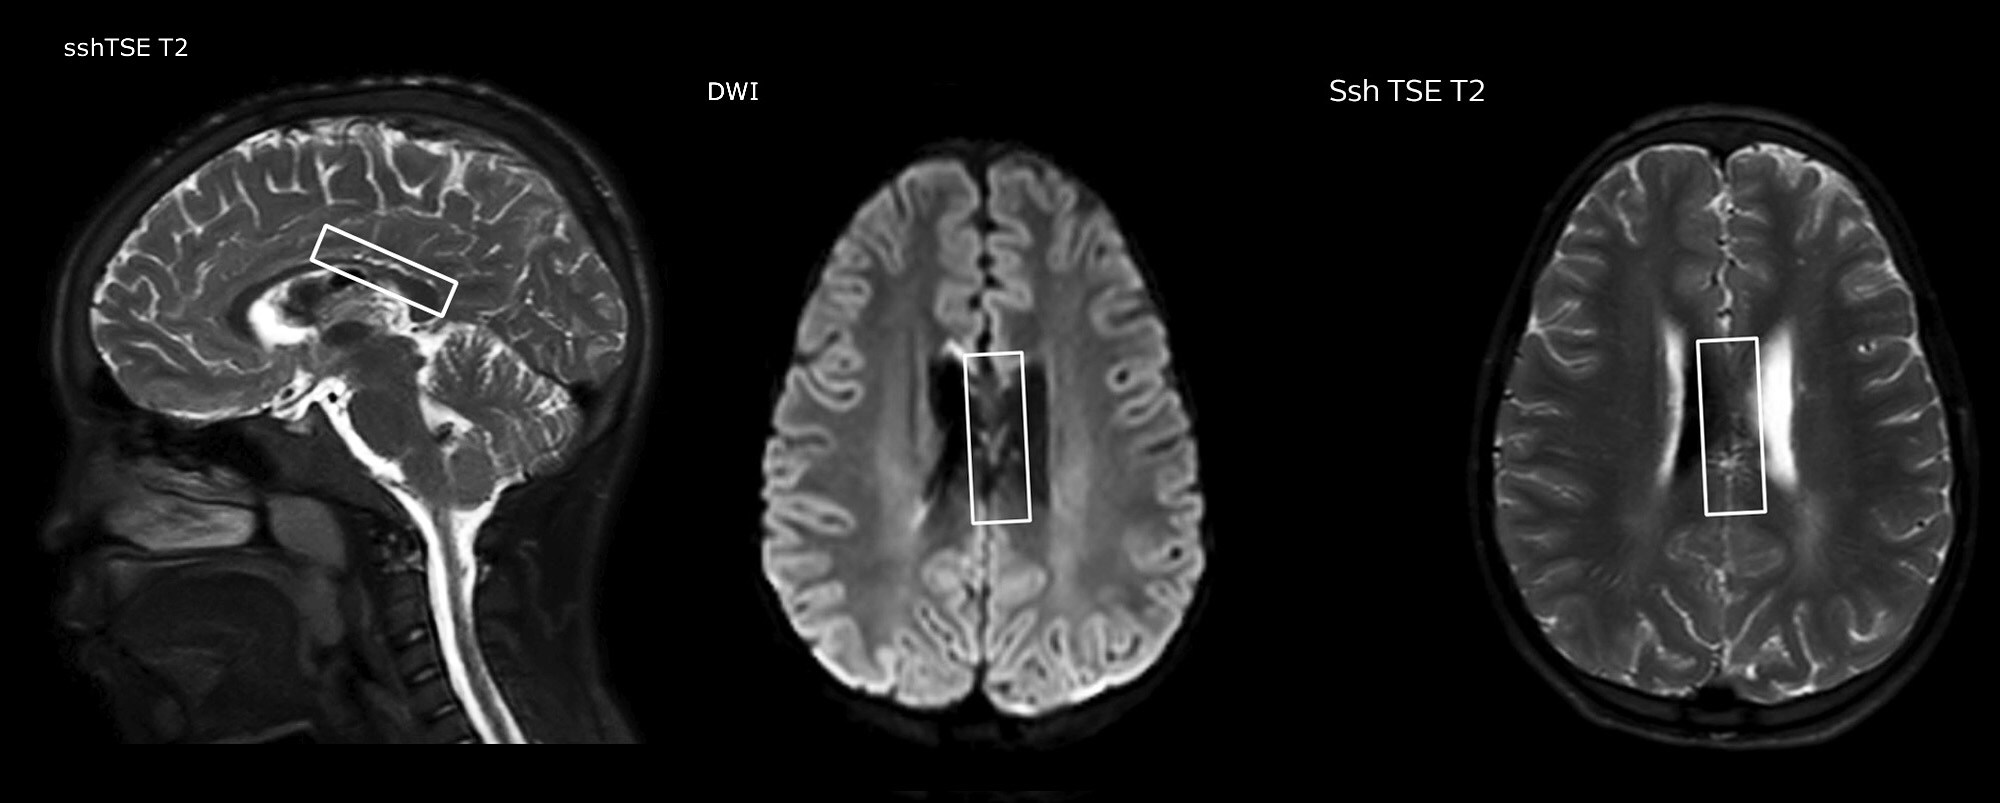

„In Kombination mit diffusionsgewichteter Bildgebung kann dieses Verfahren zu einer detaillierteren Beurteilung des Grades der Perfusionsstörung bei Patienten mit akuter Ischämie beitragen. Wir haben eine Reihe von Patienten, die unter chronischer arterieller Insuffizienz aufgrund früherer arterieller Störungen oder erworbenen arteriellen Veränderungen wie Sichelzellenanämie oder Neurofibromatose leiden. Gelegentlich manifestiert sich ein Krankheitsfortschritt beim Kind zunächst in einer reduzierten zerebralen Perfusion, bevor Schlaganfallsymptome klinisch oder in der diffusionsgewichteten Bildgebung manifest werden. Wir nutzen pCASL zur Unterstützung bei der Abgrenzung von Perfusionsstörungen.“

Anderen neuen Benutzern würde ich ebenfalls empfehlen, mit der Befundung von pCASL-Bildern im Vergleich zu anderen Standardbildgebungsverfahren zu beginnen – T2 und FLAIR und DWI –, bis sie selbst Sicherheit bei der Auswertung dieser Bilder gewinnen.“ „Der Nutzen von pCASL wird insbesondere bei Patienten mit chronischer zerebrovaskulärer Stenose deutlich, wo das Klinikteam Aufschluss darüber benötigt, wie die kompensatorischen Mechanismen des Gehirns wirken, um dessen ordnungsgemässe Durchblutung sicherzustellen. Das Klinikteam bezieht diese Funktionsweise der kompensatorischen Mechanismen häufig in die Entscheidung ein, ob ein chirurgischer Eingriff durchgeführt oder andere Massnahmen ergriffen werden.“ „Eine weitere spezielle Anwendung besteht in der Beurteilung der zerebrovaskulären Reaktivität mit einer Diamox Perfusionsuntersuchung, bei der wir zwei Sätze mit pCASL-Bildern subtrahieren.“